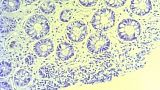

2 мл ( это мин сум, а мы делаем до 10 мл 3% перекись+200 мл физ раствора